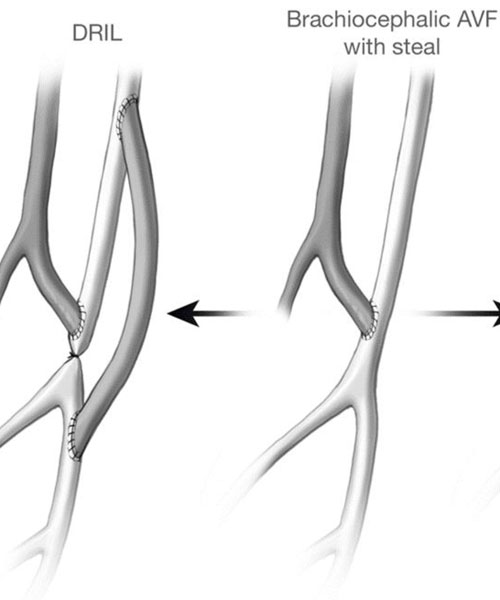

Dialysis Access – Fistula and Graft

Dialysis access is a critical aspect of the treatment for individuals with end-stage renal disease (ESRD) who require hemodialysis. Hemodialysis is a medical procedure that filters waste products and excess fluids from the blood. To facilitate hemodialysis, a reliable access point to the bloodstream is necessary.

Minimally invasive dialysis access salvage

Minimally invasive dialysis access salvage refers to procedures and interventions aimed at preserving and restoring the functionality of an existing dialysis access (e.g., fistula or graft) that may be experiencing complications or dysfunction. These minimally invasive techniques are designed to avoid the need for major surgeries, reduce patient discomfort.